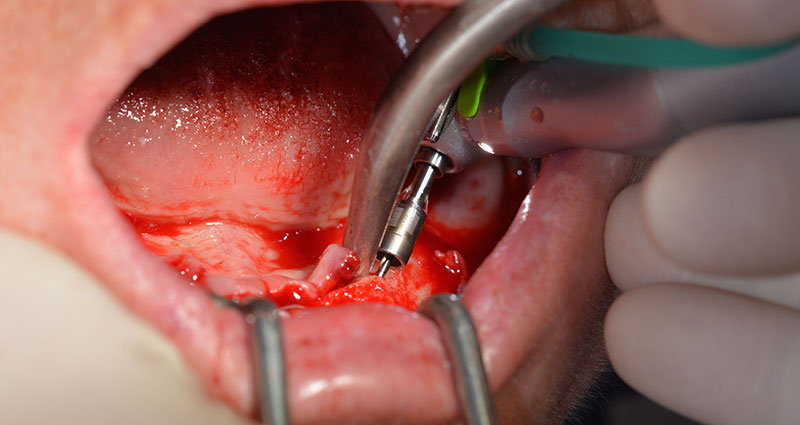

Nach der Entfernung der Unterkiefer-Restbezahnung erfolgte die krestale Schnittführung von Regio 37 bis Regio 47.

Zunächst wurde das Foramen mentale als limitierende anatomische Struktur dargestellt und die krestale Kortikalis mit dem geraden Handstück und einem großen Rosenbohrer geglättet (Abb. 4).

Hierbei zeigen sich die ersten Vorteile von Implantmed. Das chirurgische Protokoll ist bereits voreingestellt und an festen Positionen gespeichert. Die einzelnen Positionen sind sowohl über einen einfachen Druck auf die Position „P“ der Fußsteuerung anwählbar, als auch auf dem Display selbst. Die in diesem Fall an Position 1 voreingestellte Umdrehungszahl von 35.000/min wird auf dem beleuchteten Display ebenfalls groß angezeigt (Abb. 5 und 6).